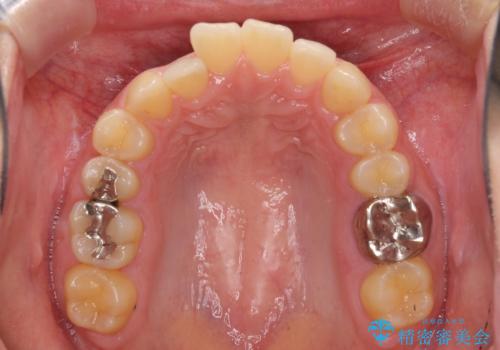

海外勤務中のインビザラインによる矯正治療

- 前歯のクロスバイトを気にして来院され患者様です。

定期的に日本には帰国するものの、日ごろは海外でお仕事をされているとのことで、インビザラインによる治療を希望されました。

トラブルが起こった時に対応ができない、来院を帰国のタイミングに合わせなければならないため治療が長期化するなど困難はありますが、ワイヤー矯正と比べると治療を進めやすいといったメリットがあるので、インビザラインにて矯正治療を行うこととしました。